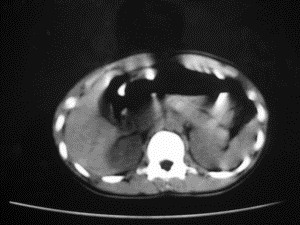

患者女,20岁,被车撞伤3小时,pe:全腹肌紧张,压痛反跳痛,以右上腹为著,肠鸣音减弱。有手术结果。![]() ![]() ![]() ![]() ![]() ![]() ![]() ![]() ![]() ![]() ![]() ![]() ![]() ![]() ![]() ![]() ![]() ![]() ![]() ![]() ![]() jiajie发言: ![]() 考虑空腔脏器穿孔。 dyqct发言:考虑:1、肝左叶外侧段断裂伤伴少量腹血。2、空腔脏器穿孔。 fangzheng发言:仅见腹腔内游离气体,提示空腔脏器穿孔。 guoke发言:胃内密度增高,肠腔内充满气体,考虑肠腔破裂出血 mmg94发言:胃后壁见一增厚软组织密度影,肝左叶前见游离气体影,左腹腔内局部肠管壁、系膜增厚。并见类圆形软组织。以上征象提示消化道管腔破裂,小肠、肠系膜挫裂伤,腹腔血肿形成。 拾荒者发言:肝实质密度不均匀,胃内见不均匀高密度影。考虑:肝挫裂伤,胃内应激性溃疡出血。 守望可可西里发言: 以下是引用jiajie在2006-6-20 15:49:00的发言:[br] [br][br]考虑空腔脏器穿孔。jiajie老师,我鼓起了很大的勇气才决定给您唱个反调儿,如果我错了,请您一定给我指出来,谢谢您了。我反复看了解剖图谱,觉得您所说的“考虑空腔脏器穿孔”上图所用箭头标明的不是游离气体。请您看以下几幅图片: ![]() ![]() ![]() ![]() ![]() ![]() ![]() ![]() 再请您看向医生老师发表的解剖图谱3幅 ![]() ![]() ![]() 这以下几幅图,我认为是肝包膜下积血。不过,说实在话,我没有发现有明显的肝挫裂伤。不对的地方请您一定指出来,再次感谢您了,jiajie 老师! ![]() ![]() ![]() ![]() 这下面几幅图片,我认为有明显的左中上腹部小肠损伤。 ![]() ![]() ![]() ![]() ![]() ![]() ![]() ![]() jiajie 老师,估计我说的是错误的,但我实在闹不明白,请您一定不要笑话我,并指出我的错误,以便于我减少工作中的失误。再次感谢您了,jiajie 老师! 至于胃内的不均匀高密度,我认为拾荒者战友说的有道理,胃内应激性溃疡出血和胃内容物混合所致。 手术结果:左肝叶(iv段)前缘长约8cm挫裂伤口,舌叶根部下< |